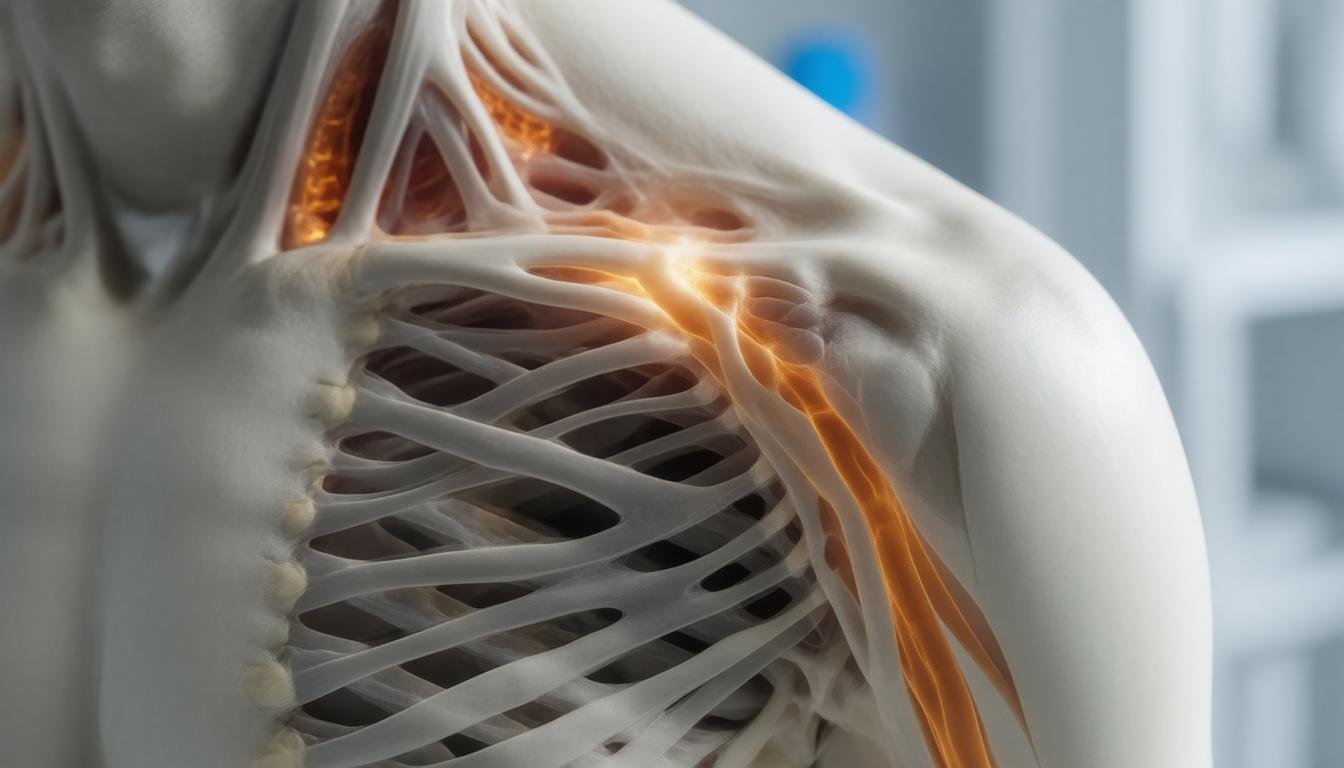

Wat is peesontsteking in de schouder?

Peesontsteking in de schouder: oorzaken en aanpak, wat houdt dat eigenlijk in? Nou, een peesontsteking, of tendinitis zoals de dokters het soms noemen, is gewoon een fancy term voor die irritante ontsteking in de pezen rondom je schouder. Ik weet het, klinkt niet zo fijn! Het kan ontstaan door overbelasting, bijvoorbeeld als je veel overhead acties doet zoals traplift installeren, schilderen of gewoon lekker een potje tennis spelen. Voor je het weet, voel je die pijn bij elke beweging en komt zelfs die simpele taak als een glas uit de kast pakken als een hele opgave. Maar geen zorgen! Vaak kun je het aanpakken met wat rust, ijs op de pijnlijke plek en wellicht wat fysiotherapie. En ja, misschien even die overhead bewegingen op een lager pitje zetten. Iedereen heeft wel eens zo’n blessure gehad, dus je bent echt niet alleen. Heb je het idee dat je het niet meer alleen kunt fixen? Dan is het slim om die arts om advies te vragen. Er zijn genoeg opties om je weer in beweging te krijgen!

Oorzaken van peesontsteking in de schouder

Als je ooit last hebt gehad van een peesontsteking in de schouder, dan weet je dat het behoorlijk vervelend kan zijn. Het is die pijn die je belemmert om je arm op te tillen, of bedenkt je ineens dat je favoriete hobby misschien niet meer zo leuk is. Maar wat zijn eigenlijk de oorzaken van zo’n peesontsteking in de schouder? Laten we er eens in duiken.